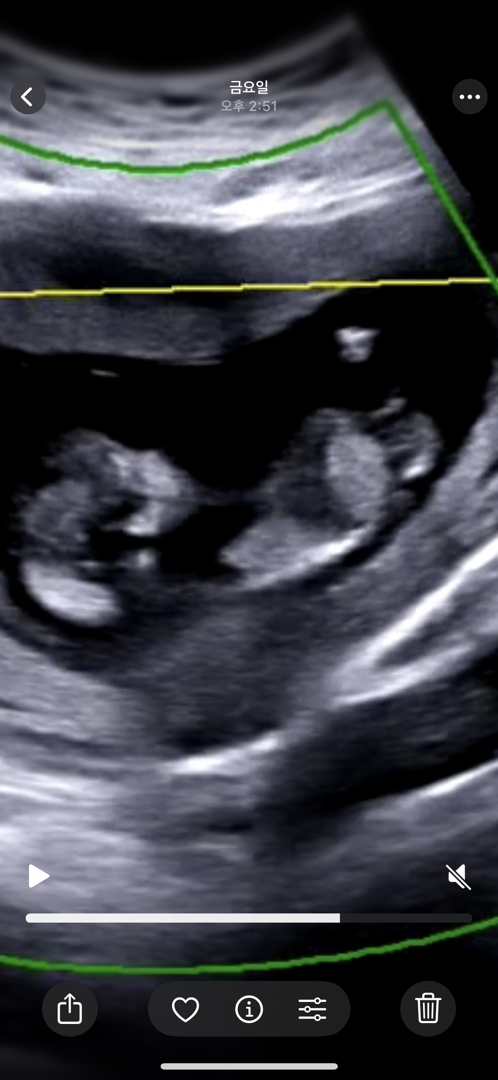

12주 각도법 잘보시는분 !! 셋째라 제발 부탁드려요 🙏🏻

저 정도면 아들각 인가요 ?!!! 셋째라 너무 궁금해서 하루하루 각도법만 보게 되네요 ㅠㅠ ! ..